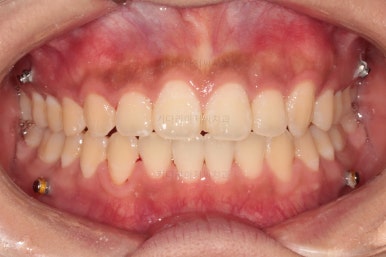

치열의 고른 느낌 좋고요.

덧니, 교합, 중앙선 등 모든게 좋아졌네요.

부산치아교정치과 전후 비교해 보겠습니다.

교합, 맞물림, 중앙선, 덧니, 입매, 앞니위치 및 각도 모든게 잘 마무리 되었습니다.

비발치로 오히려 입이 들어가게(악궁확장이나 치간삭제(공간확보의 목적) 없이도) 할 수 있었던 부산치아교정치과 좋은 치료였습니다.